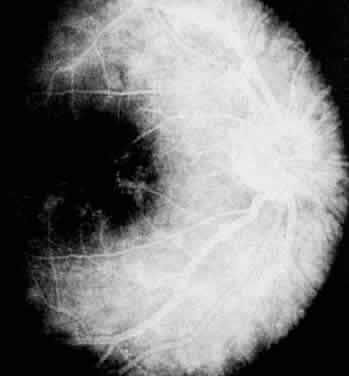

FLUORESCEIN ANGIOGRAPHY AND VITREOUS FLUOROPHOTOMETRY In pars planitis, fluorescein angiography shows diffuse leakage from the retinal venules and capillaries, without any predilection for the inferior retinal vasculature (Figs. 5 and 6).28 Similarly, vitreous fluorophotometry in patients with pars planitis also shows no predilection for vascular leakage in the inferior peripheral retina.29 These findings suggest that snowbank is most likely a sequela from ocular inflammation, that inferior peripheral retina periphery is not the source of inflammation in pars planitis, and that pars planitis is not a localized inflammatory response of the inferior retina.